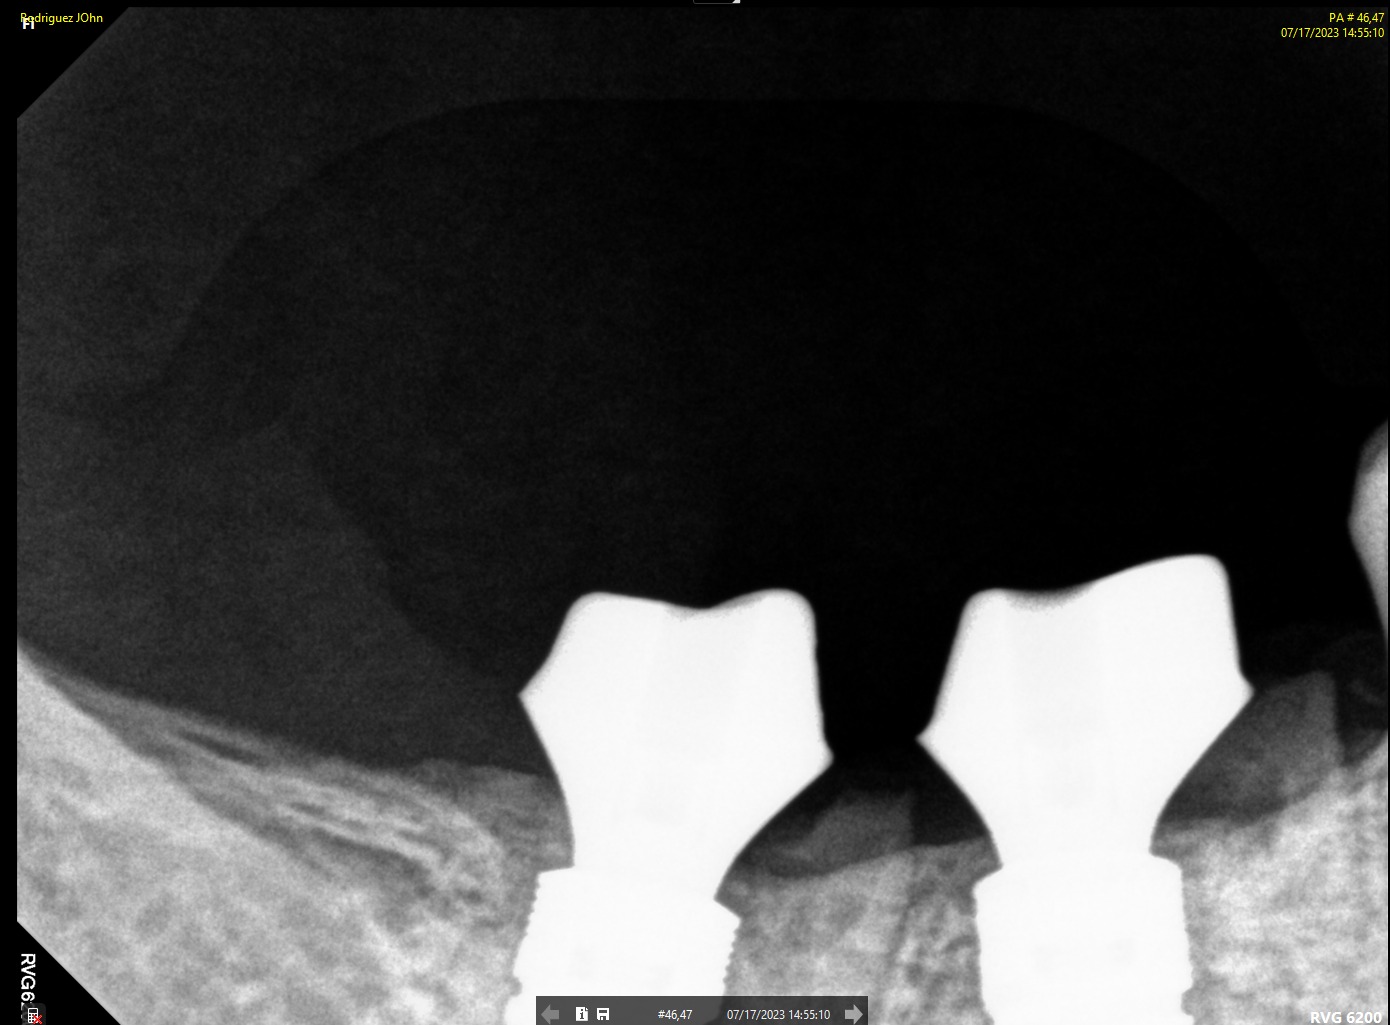

SURGERY

A flap approach was performed under local anesthesia. Osteotomies were prepared following the digital treatment plan, respecting biological principles and anatomical limitations. Two DSI Premium Mountless Implants were placed with high primary stability. The implants were positioned to allow optimal emergence profile and long term crestal bone preservation. Primary closure was achieved, and DSI Concave Healing Caps were placed to support soft tissue architecture during healing.

FINAL RESTORATION

Following successful osseointegration:

• Digital impressions were taken

• Screw-retained implant-supported restorations were fabricated using custom abutments

Final restorations demonstrated:

• Proper occlusal integration

• Natural emergence profile

• Radiographic confirmation of stable crestal bone levels

Clinical and radiographic images confirmed successful functional and esthetic outcomes at delivery.